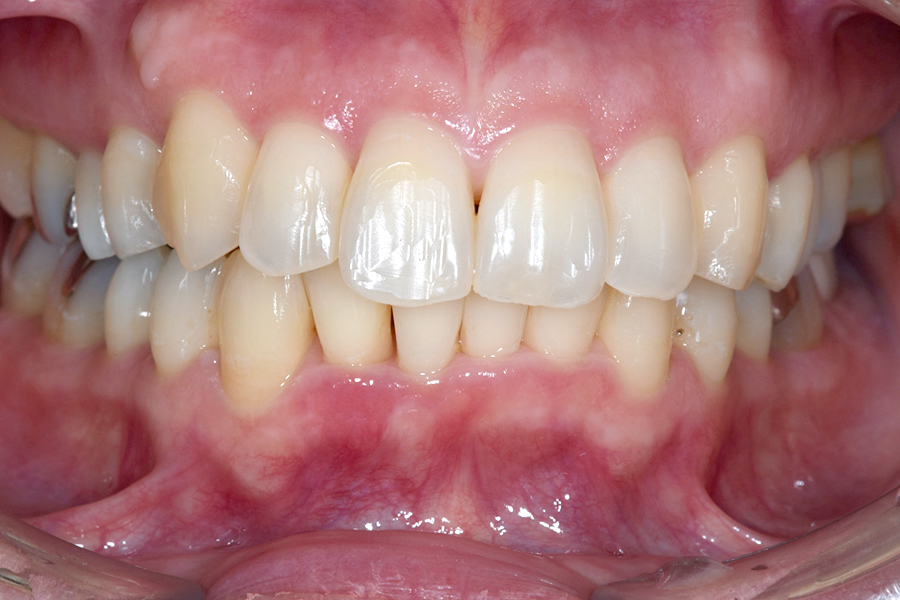

| 主訴 | 見た目を治したい、歯を白くしたい |

|---|---|

| 治療期間 | 1年6か月 |

| 治療費 | マウスピース矯正と ホームホワイトニングセット 1,022,350円(税込) |

| 治療内容 | 目立ちにくいマウスピース矯正 (非抜歯矯正) 歯と歯の間に隙間をつくることにより、歯列弓を広げながら治療を行いました。 また矯正用マウスピースをトレー代わりにし、ジェルを入れてホームホワイトニングを同時に行っております。 |

| 治療のリスク | ・後戻りする可能性があるのでリテーナーを最低でも矯正期間以上はつける必要があります。 ・ホワイトニング後、一時的に痛みが出る場合があります。 |